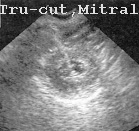

En la Fig 57, se está procediendo a punzar la mitral.